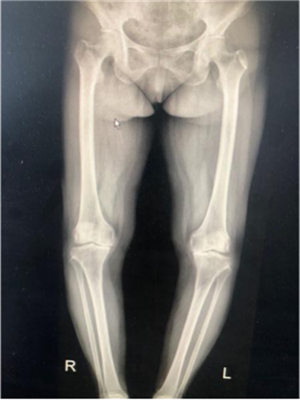

67歲的徐女士是陜北定邊縣人,10年來,她因?yàn)殡p膝關(guān)節(jié)疼痛,行走困難,不能上下樓梯,更無法像常人一樣下蹲,這給徐阿姨和她的家庭帶來了巨大的困擾。經(jīng)多方打聽,徐阿姨慕名找到張富軍主任,張主任詳細(xì)檢查后發(fā)現(xiàn)徐阿姨為雙側(cè)嚴(yán)重的骨關(guān)節(jié)炎并滑膜軟骨瘤病,需要進(jìn)行全膝關(guān)節(jié)置換術(shù)??紤]到患者有多種基礎(chǔ)病合并癥,張主任帶領(lǐng)其團(tuán)隊(duì)認(rèn)真研究后制定了詳細(xì)、周密的手術(shù)方案,做好圍手術(shù)期的準(zhǔn)備,決定采用最新技術(shù)的Vanguard CR E1假體雙膝膝關(guān)節(jié)置換術(shù)。

?。ㄊ中g(shù)前、手術(shù)后對(duì)比)

5月29日,徐阿姨如期進(jìn)行了雙側(cè)全膝關(guān)節(jié)同期置換術(shù)。術(shù)中發(fā)現(xiàn)徐阿姨膝關(guān)節(jié)退變嚴(yán)重,有大量的滑膜軟骨瘤,清除病變后又發(fā)現(xiàn)她前交叉韌帶缺失后交叉韌帶纖細(xì),即決定采用限制性較高的E1 AS墊片,該假體極大的提高了手術(shù)安全性,降低了手術(shù)風(fēng)險(xiǎn)和創(chuàng)傷,手術(shù)歷時(shí)2小時(shí),患者術(shù)后恢復(fù)良好。手術(shù)后第二天,徐阿姨就可以扶著助步器下地活動(dòng),目前已可以徒步行走、上下樓梯。